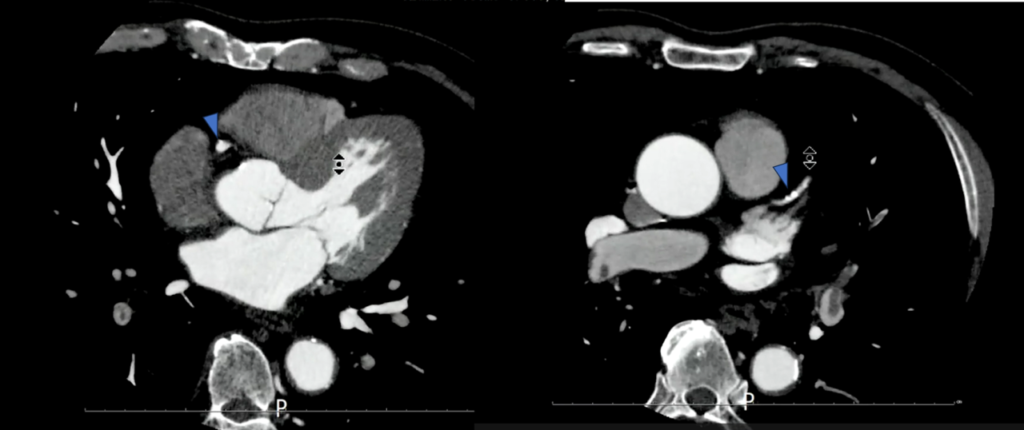

冠動脈に有意な狭窄はなかったのですが、先ほどの症例と同じように

肺動脈にfillifng defectを認めます。

造影後”15分後”に追加で撮影した画像がこちらです。

造影後15分後でも造影効果がわずかに残っていました。

これを見ると、冠動脈CTでは右肺動脈に大きい血栓があるように見えましたが、左肺動脈の方が血栓サイズが大きく、これによる左胸の痛み症状だったのではないかと考えられました。

下肢静脈も15分後でもわずかに造影効果が残っており、左浅大腿静脈にfilling defectを認めました。

造影剤量も60mlと通常の深部静脈を観察するには少ない量でしたが、15分後の撮影でもなんとか観察することができました。

こちらも管電圧を下げて撮影しました。時間経過で造影効果が低くなった肺動脈や深部静脈の造影効果を上げてなんとか観察することができた症例です。